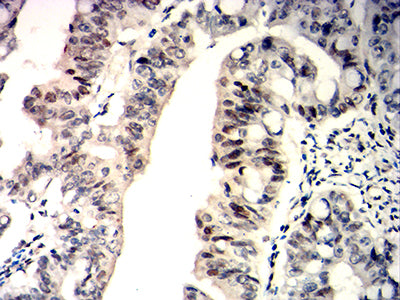

Immunohistochemical analysis of paraffin-embedded human rectum cancer tissues using WT1 mouse mAb with DAB staining.